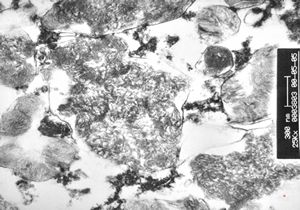

M, 44y. | Gaucher disease … liver